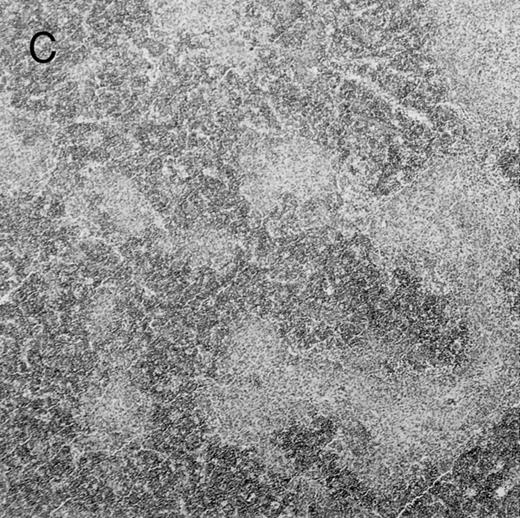

Histologic findings. Organs were collected at different times after BMT and tissue sections were stained with hematoxylin and eosin. Original magnifications for spleen (left) and liver (right) are ×40 and ×100, respectively. (A) B6 mice receiving FVB BM plus EpTK T cells. (B) Control group receiving BM only.

(C) B6 mice receiving FVB BM plus EpΔTK T cells and treated with GCV. (D) B6 mice receiving FVB BM plus EpΔTK T cells, treated with GCV, and developing a late onset GVHD (day 54).

Protection from GVHD was slightly less efficient in the group receiving EpΔTK CD3+ T cells. The survival rate was 79% at day 60 and 67% at day 120 (Fig 2B). However, two different outcomes must be distinguished. On the one hand, a majority of mice behaved as GCV-treated animals receiving EpTK T cells. They were apparently healthy, presented no skin lesions during a 120-day observation period, and showed complete donor-type hematologic reconstitution. There were no histological signs of GVHD in the spleen or liver (Fig 4C).

On the other hand, 5 of 19 mice exhibited signs suggesting the occurrence of a delayed GVHD (Table 1). Clinically, these animals presented weight loss and/or skin lesions on ears, neck, limbs, or abdomen, but only after day 40. In the absence of any further GCV treatment, 2 mice died 14 and 29 days after the occurrence of these signs (Table 1A) with histological signs of severe GVHD (Fig 4D). These results suggest that, in these mice, the 7-day GCV treatment was sufficient to prevent early, but not delayed GVHD.